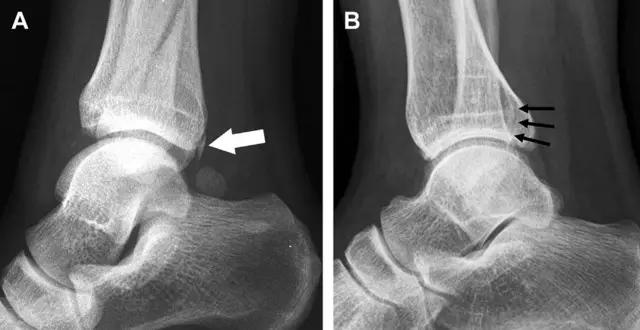

18 距骨外侧突骨折

距骨外侧突骨折常因踝外翻背屈时,跟骨上外侧面撞击距骨外侧突下缘导致,或偶尔由踝内翻引起,被称为「滑雪板者骨折」。这种骨折只能在踝关节正位片上发现,而且外踝远端表面软策划肿胀往往是一个重要线索(图 4)。

图 4 距骨外侧突骨折。A 正位片示内翻损伤所致的距骨外侧突撕脱性骨折(箭头);B 另一位患者,踝外翻损伤导致典型的「滑雪板者骨折」,X 片上可见一较大的三角形骨折块(方框);C 第二位患者的 MRI 矢状位 T1 加权像示横行骨折(箭头)